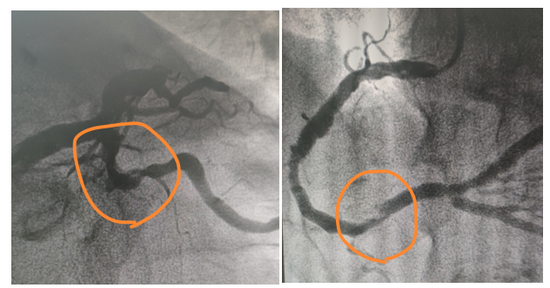

左图:回旋支近段高度狭窄 右图:右冠状动脉远段一处局限狭窄伴斑块

术后效果图,患者回旋支严重狭窄病变解除!